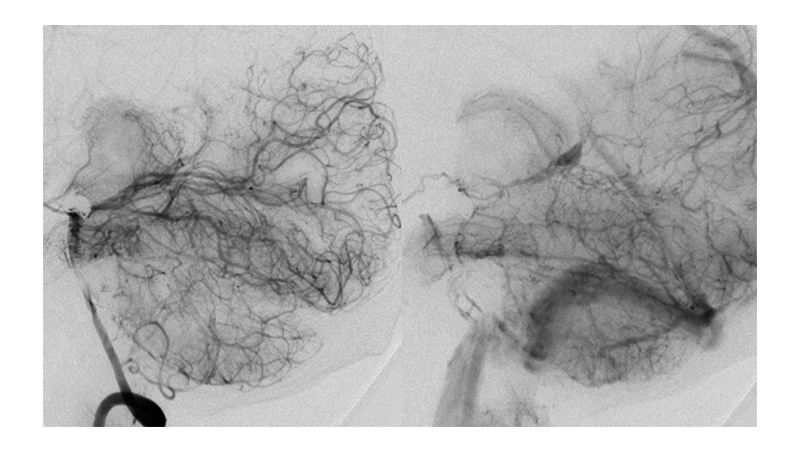

Εικόνα 6, 7, 8: Πλήρης απόφραξη του ανευρύσματος με coils. Ταυτόχρονα η αγγειοπλαστική του ανωτέρου τριτημορίου της βασικής αρτηρίας και των οπισθίων εγκεφαλικών έχει αποκαταστήσει την ροή αμφοτερόπλευρα.

Βλέπουμε την αποκατάσταση της διαμέτρου των οπισθίων εγκεφαλικών αρτηριών αλλά και της βασικής αρτηρίας, που έχει ως αποτέλεσμα την βελτίωση της παρεγχυματογραφίας του σπονδυλοβασικού συστήματος.

Εικόνα 9: Το εκμαγείο των coils μετά τον εμβολισμό.